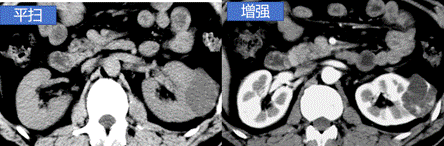

CT平扫是普通CT扫描,用于全身各部位检查,能提供病变的初步定位,显示病灶的基本形态、大小等,是临床常规的检查方法。平扫是相对于增强扫描而言,是最普通、最基础的CT检查。然而,有些疾病或病变在平扫CT上可能呈现模糊或难以辨认的特征,这时就需要进行CT增强扫描。

增强CT是在检查前先将含碘的对比剂注射进静脉后再进行扫描,是对平扫CT的补充,由于碘对比剂进入血液后,血液中含碘浓度升高,在病变部位与器官中的碘浓度形成密度差异,这样显影就更加清晰,更有利于对病灶范围、数量及性质等做出判断。因此,增强扫描是对CT平扫的补充,可以理解为CT平扫的升级版。

提高病变的检出率:在一些情况下,疾病早期病变较小,或者病变与周围正常组织的密度差异较小,平扫CT可能无法明确显示病变。通过增强CT,病灶或异常区域的对比度增加,病变更容易检测和诊断。